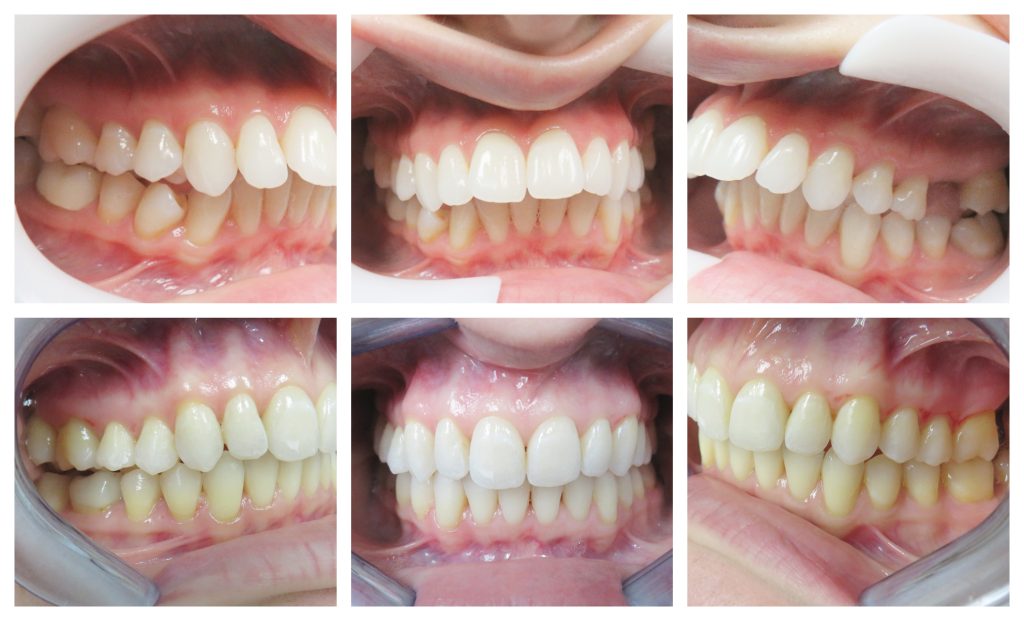

Understanding the significance of regular dental exams and cleanings is essential for maintaining long-term oral health. At Downers Grove Dental Spa, located at 640 Ogden Ave, Suite E, Downers Grove,…